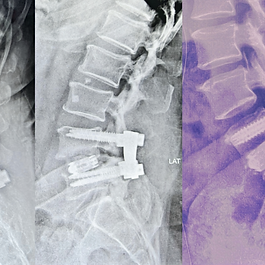

Spinal Fusion Surgery

X-Ray of lumbar spine showing TLIF surgery